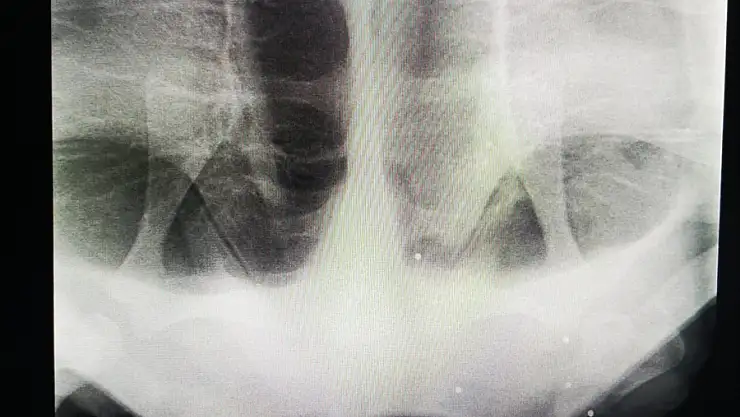

Burada veterinerlerce muayene edilen ve röntgeni çekilen 26 kilogram ağırlığındaki dişi kaplumbağanın, ateşli silahla vurulmuş olduğu belirlendi.

Kaplumbağanın ayrıca sol yüzgecinde 8 santimetre uzunluğunda derin bir yırtık, yüzünün sol tarafında 7 santimetre büyüklüğünde doku kayıplı bir yara, kabuğunda ise 4,5 santimetre uzunluğunda bir çatlak bulunduğu tespit edildi.